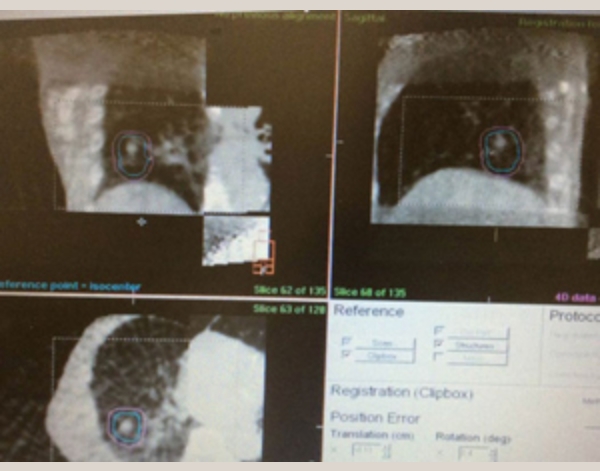

呼吸性移動の管理

治療前の毎回の動画撮影

実際は腫瘍も肺全体も呼吸とともに上下左右に動いています。腫瘍(白い点)が照射野内であることを毎回確認して実施

放射線治療中の動画の確認(必要時に行う)

大線量が放出されている脇で

CTを撮影して腫瘍位置を検証